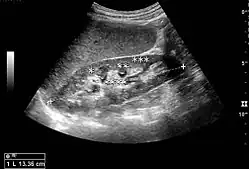

Figure 18. Renal stone located at the pyeloureteric junction with accompanying hydronephrosis.[1]

With US, larger stones (>5–7 mm) within the kidney, i.e., in the calyces, the pelvis and the pyeloureteric junction, can be differentiated, especially in the cases with accompanying hydronephrosis (Figure 18 and Figure 19). Hyperechoic stones are seen with accompanying posterior shadowing. Additional twinkling artifacts below the stone can often be seen using Doppler US. Large stones filling the entire collecting system are called coral stones or staghorn calculi and are easily visualized with US (Figure 20). Stones in the ureters are usually not visualized with US due to the air-filled intestines obscuring the insonation window. However, ureteral stones near the ostium can be visualized with a scan position over the bladder. An exam of the ureteric orifices and the excretion of urine to the bladder can be performed by inspecting the ureteric jets in the bladder with color Doppler US.